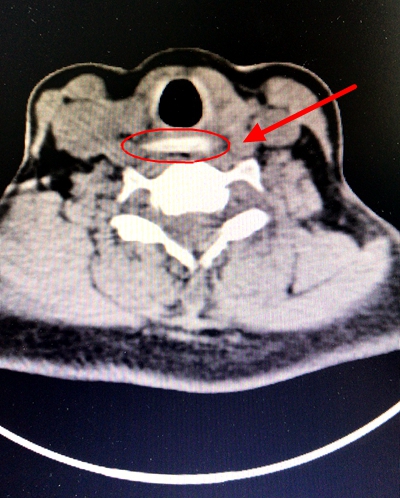

杨大哥家人立即带他来到了湘雅常德医院急诊,行食道ct三维重建,见枣核样异物横行于第六颈椎下缘,食道第一狭窄处稍下方, 异物右侧尖端与右侧颈总动脉基本相接壤,左侧与同侧颈总动脉距离非常接近。

急诊科立马联系耳鼻喉科主任田湘娥教授,田教授查看患者的基本情况后指出:患者情况比较紧急,时间紧迫,一旦颈总动脉破裂,后果不堪设想,患者就会有生命危险。完善相关检查化验,考虑急诊全麻下硬性食道镜下取出异物,食道镜选择管径最大的,并且应尽量靠左侧操作,全麻肌松量要足,尽可能避免异物右侧尖端因操作不当导致刺破右侧颈总动脉引起致命性大出血。